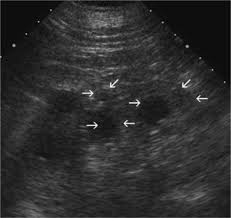

Lithium Toxicity Wikipedia from upload.wikimedia.org Acute lithium toxicity is generally subdivided into three grades: Some symptoms may last for a year after levels return to normal. Scope of guideline these guidelines include advice to prescribers and other healthcare Lithium toxicity is another term for a lithium overdose. A summary table to facilitate emergent management of lithium poisoning is provided. Often only cessation or reduction of lithium doses is sufficient. What is lithium used for lithium is commonly prescribed by psychiatrists to manage recurrent. Initial bloods should include a lithium level and uesalong with a clinical assessment of fluid status and signs of established neurotoxicity (confusion, increased tone, tremor, hyperreflexia, clonus).